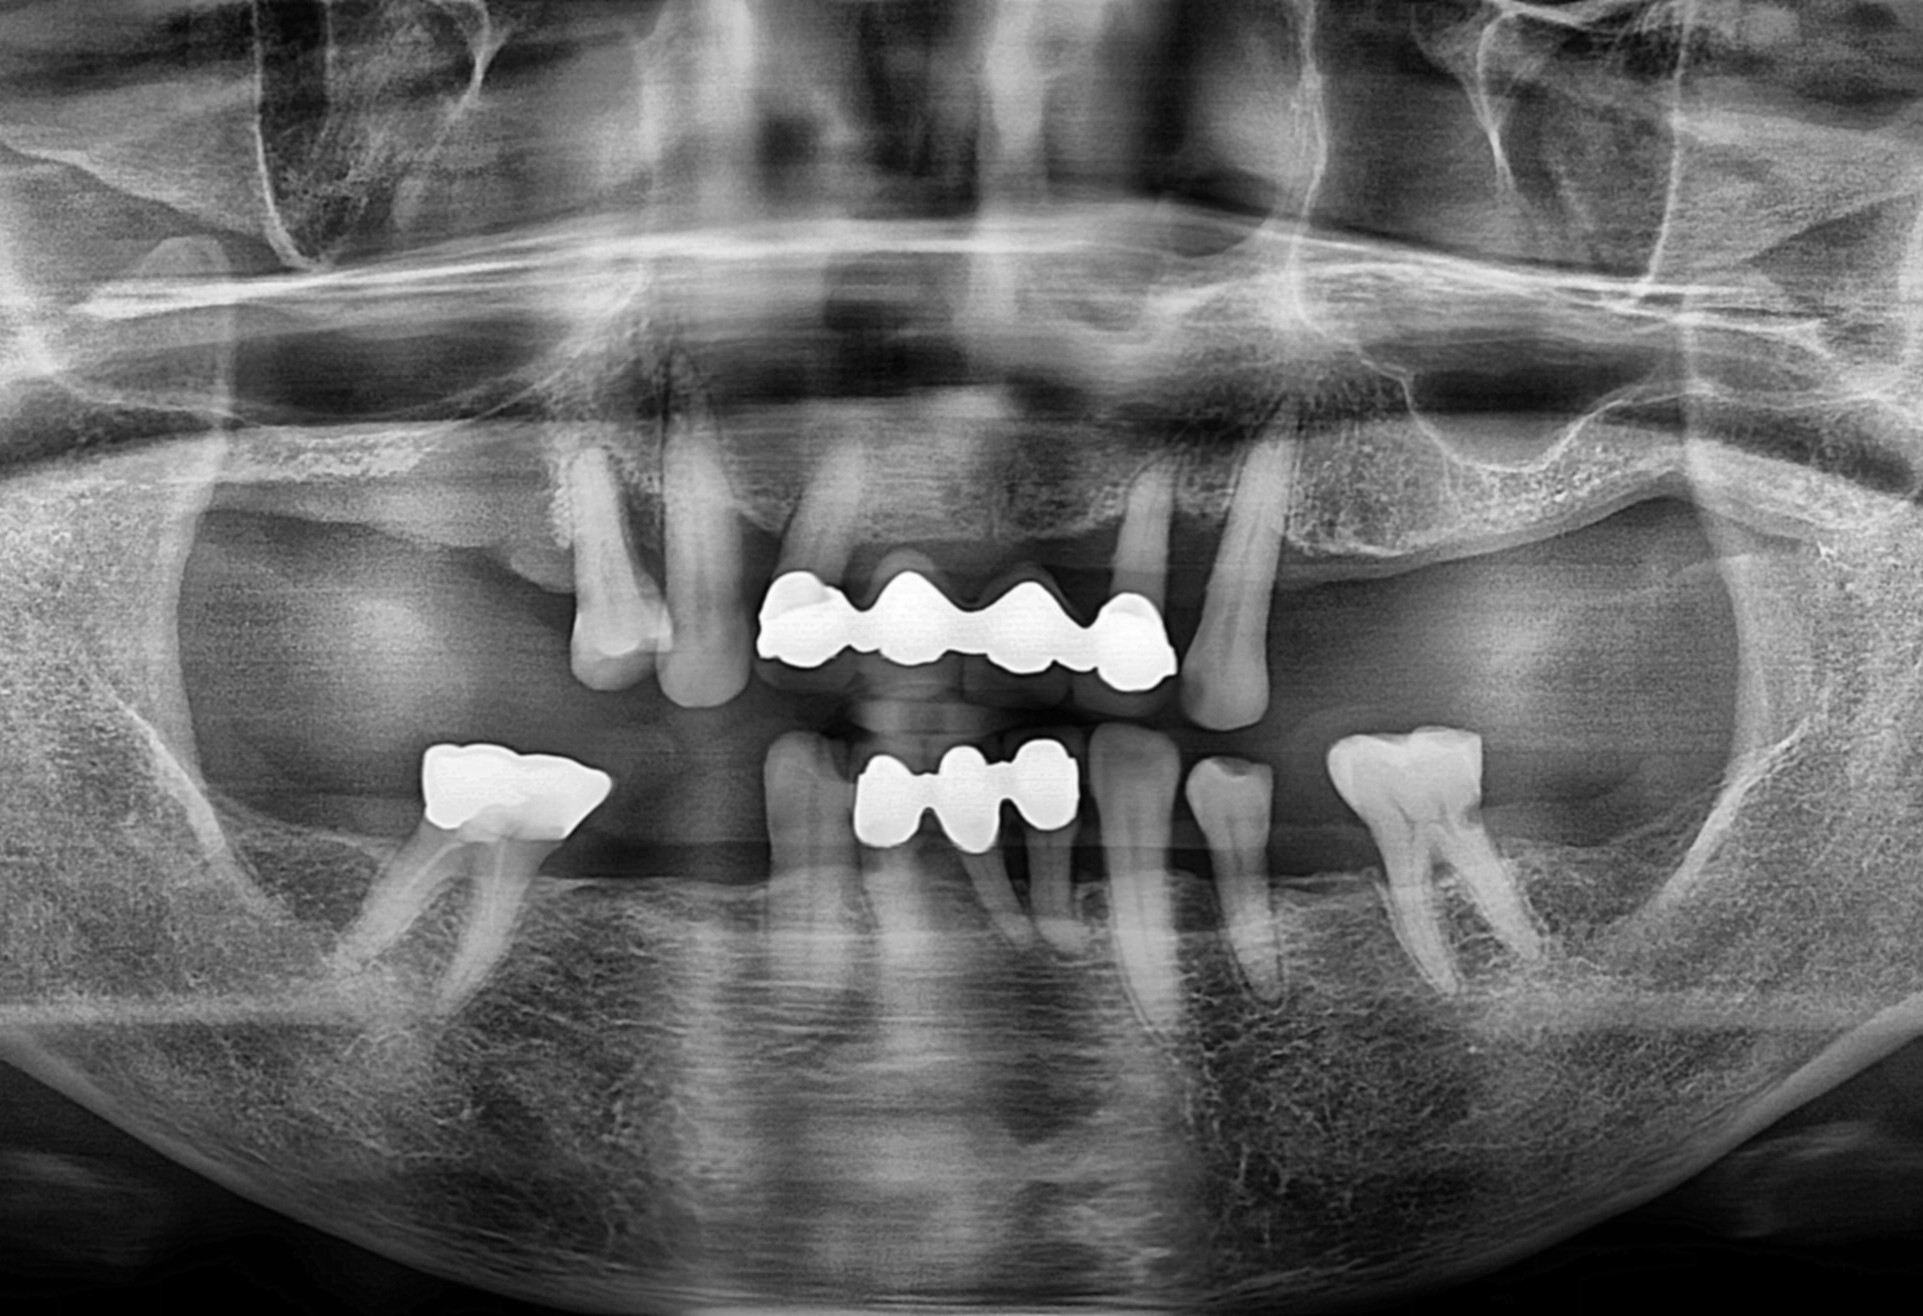

치료 전 X-ray

전반적으로 잇몸 건강이 무너진 상태에서 오랜 보철물 사용으로

전치부만 교합이 되는 상황이었습니다. 잇니 치아가 전체적으로 많이 흔들려 식사를 거의 하지 못하고 계셨습니다.